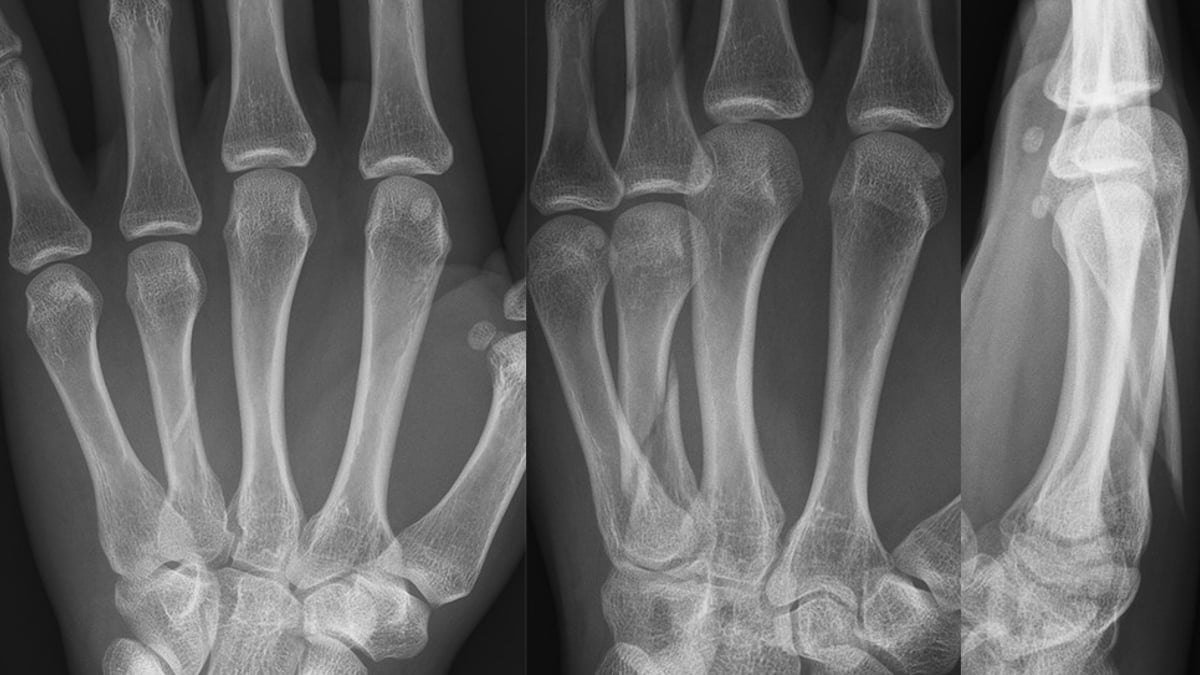

En forskningsstudie ledd från Akademiska visar att en ny behandlingsmetod för frakturer på mellanhandsbenen, fokuserad på aktiv träning, ger lika bra resultat som traditionell behandling med operation och gipsning.